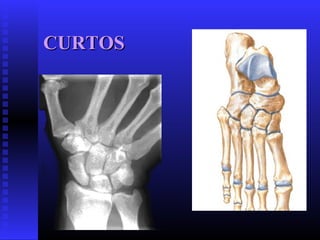

 CURTOSCURTOS

CURTOSCURTOS